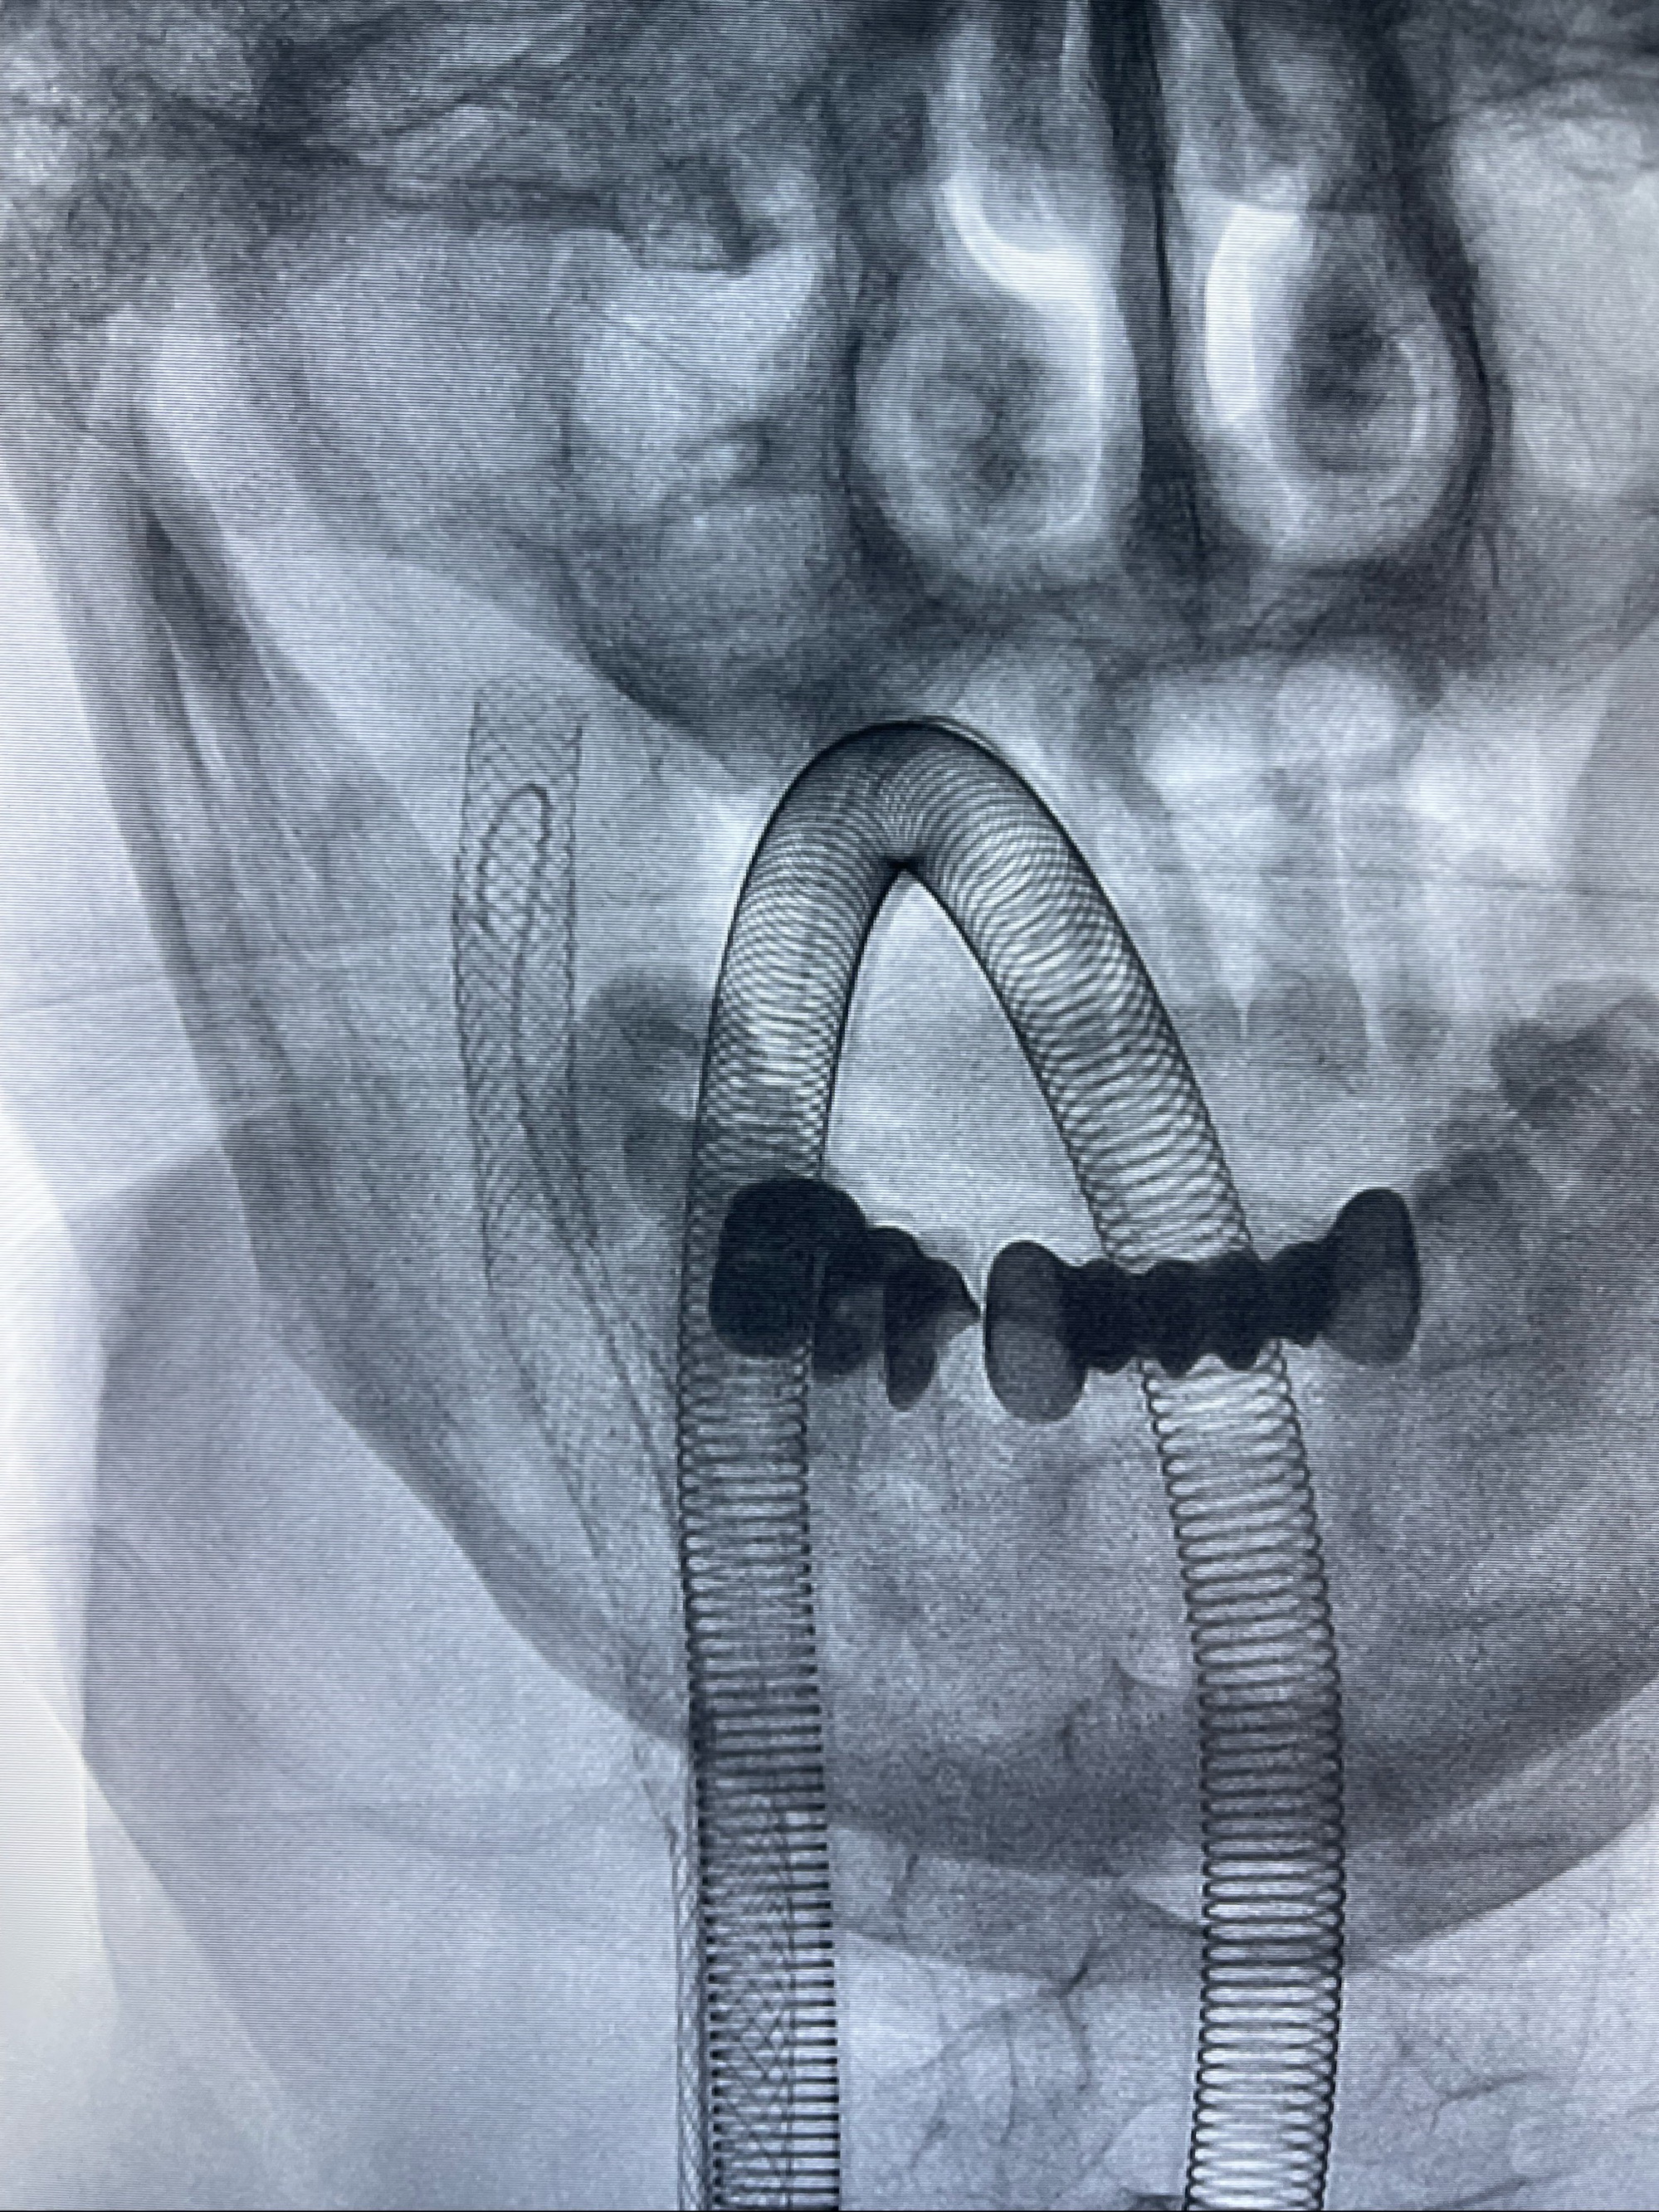

088NeuroMAX100cm长鞘在125cmMPA及黑泥鳅导丝引导下超选择性插入右侧颈内动脉支架内

经导引导管造影显示支架远端颈内动脉不规则狭窄伴局部充盈缺损,同时行全身肝素化5ml

重新行“路径图”,支架导管在微导丝引导下超选择性插入至右侧颈内动脉眼段,4.5-50mmLeo支架释放,远心端位于海绵窦段,近心端位于岩骨段狭窄段以近

即刻造影显示支架贴壁佳

路径图下,5.5-50mmLeo支架导管在微导丝引导下超选择性插入远段Leo支架内

两枚支架部分重叠

多次确认支架位置及打开贴壁情况

支架完全打开,近心端位于原颈动脉支架远心端内